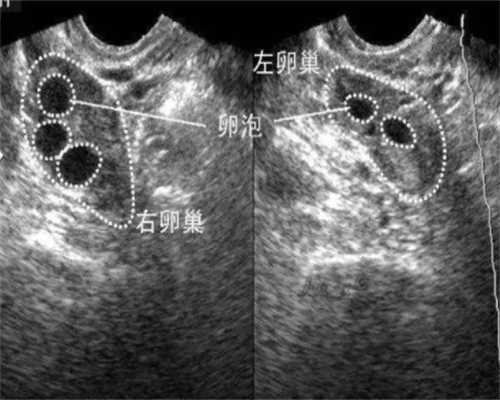

高龄供卵价格去医院怎么查卵泡(去医院监测卵泡的流程)

代生公司电话监测排卵和监测卵泡是一回事吗_排卵期能监测卵泡吗

打尿促性素卵泡一天长多少?

国内代生孩子中介,卵巢畸胎瘤患者打hmg卵泡一天长多少(打hmg卵泡一天长多少)